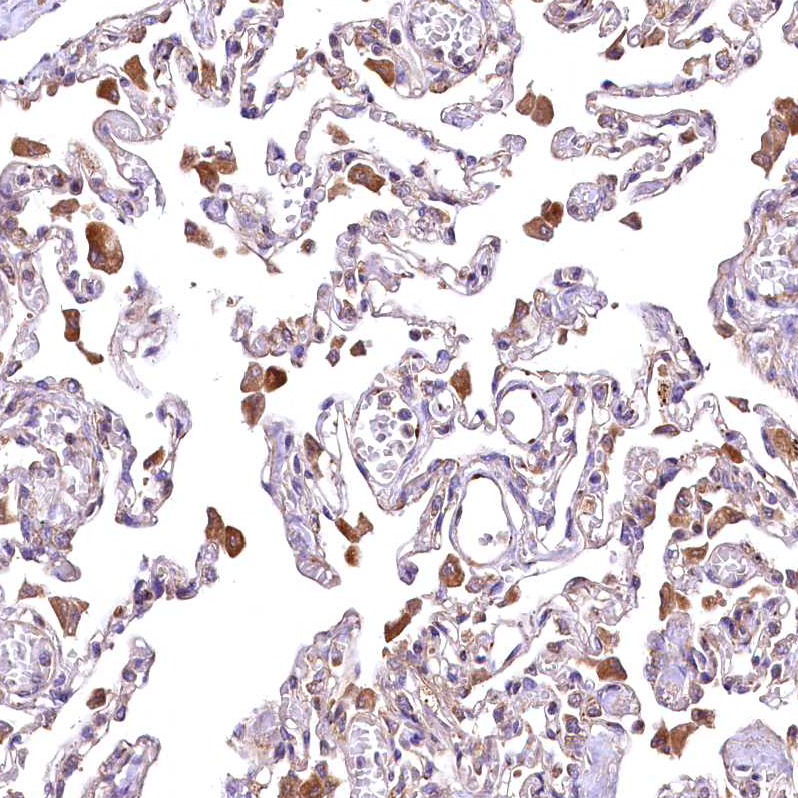

Immunohistochemical staining of human lung shows moderate cytoplasmic positivity in macrophages.